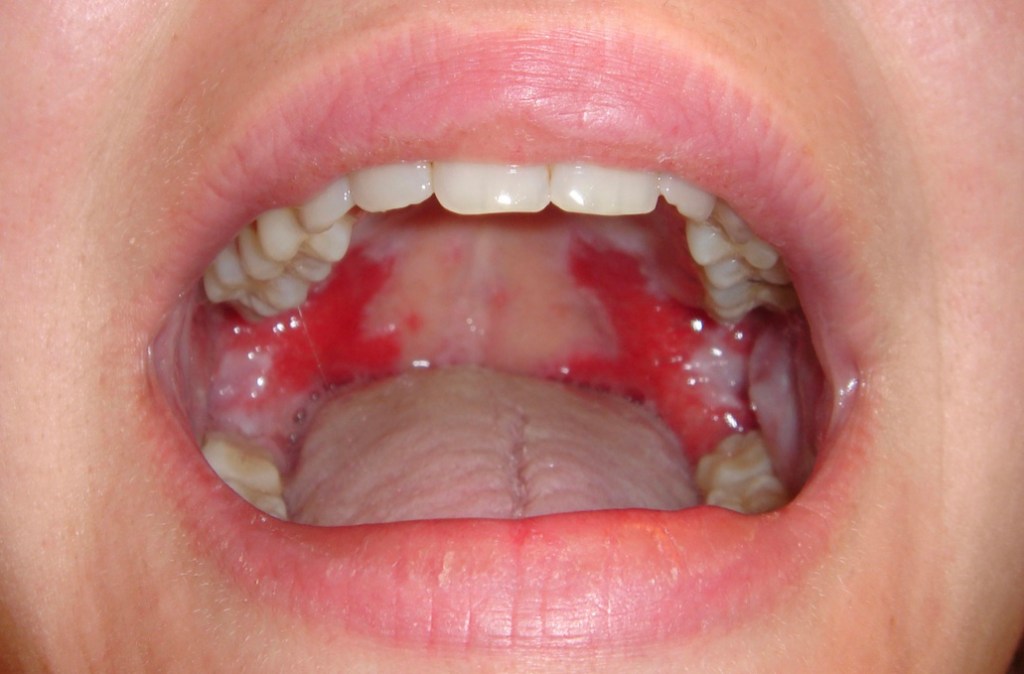

2. Bacterial (streptococcal pharyngitis and tonsillitis)

The throat shows small petichiae (bleeding spots) on the palate. If tonsillitis coexists, the tonsils are enlarged and show pus oozing from them and the lymph nodes in the neck are enlarged. Streptococcal infection is the commonest cause for a sore throat even more common than viruses. Recurrent streptococcal infection may predispose patients to Rheumatic fever and cardiac disease. Bacterial pharyngitis may also be caused by Neisseria gonorrhoea, Mycoplasma and chlamydia species. Antibiotics would be needed in many cases.